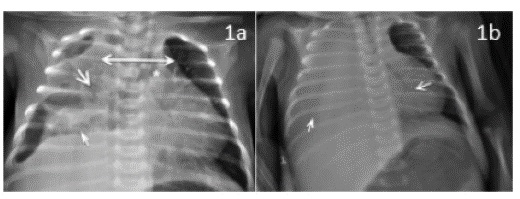

Laboratorios iniciales, con hemograma que reporta leucocitos de 19 3 50 x 103 cel/μL, N: 60 %, L 23 %, M 15 %, Eos 0,3 %, Baso 1,7 % y plaquetas 687 000 x 103/ μL, Hb 11,2 gr/dl, Hto 32,9 % y PCR de 259 mg/dl. Además, se toma panel viral que reporta positivo para virus sincitial respiratorio (VSR). Hemocultivos iniciales negativos. La radiografía de tórax a su ingreso muestra consolidación parenquimatosa del lóbulo superior e inferior del hemitórax derecho. Adicionalmente, hay presencia de cámaras aéreas del vértice pulmonar derecho y neumomediastino anterior (otros hallazgos asociados en Figura 1a). Se continúa con antibióticos de primera línea, pero por gran compromiso radiológico, se cambia a las 12 horas a Cefepime-Clindamicina;y esta se cambia a vancomicina (72 horas postingreso) por deterioro clínico, dado por fiebre, taquicardia y falla ventilatoria. Rx de tórax de control evidencia velamiento del hemitórax derecho (Figura 1b). Eco pleural reporta derrame pleural del hemitórax derecho. Presenta falla respiratoria, y es valorado por cirugía pediátrica, quien realiza toracostomía cerrada con salida de material purulento que se envía a estudio. Hay compromiso hemodinámico, por lo que requiere soporte inotrópico y altos parámetros ventilatorios por acidemia respiratoria e hipoxemia. Es llevado a tomografía contrastada, donde se evidencia empiema tabicado en el hemitórax derecho, por lo que es llevado a cirugía; se realiza decorticación pulmonar hasta lograr expansión pulmonar. Resultado de Gram de líquido pleural cocos Gram positivos escasos, reacción leucocitaria abundante, con reporte final de cultivo de líquido pleural de SARM, resistente a Clindamicina (ver Tabla 1). Dado el reporte, se suspende Cefepime. La muestra de patología reportó material fibrinopurulento, con focos de necrosis de licuefacción, colonias de bacterias cocoides en racimos, organizados en abscesos y dispersos en el parénquima adyacente; los septos presentan infiltrado inflamatorio; algunos vasos muestran trombosis; la superficie pleural presenta hemorragia (Figura 2a,2b). La evolución clínica muestra mejoría; completa catorce días de vancomicina y egresa para seguimiento ambulatorio.